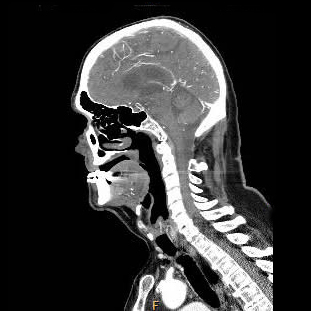

| Computertomographie mit aktuellen Dosisreduktionsverfahren | ||

| Kopf | 1-2 | |